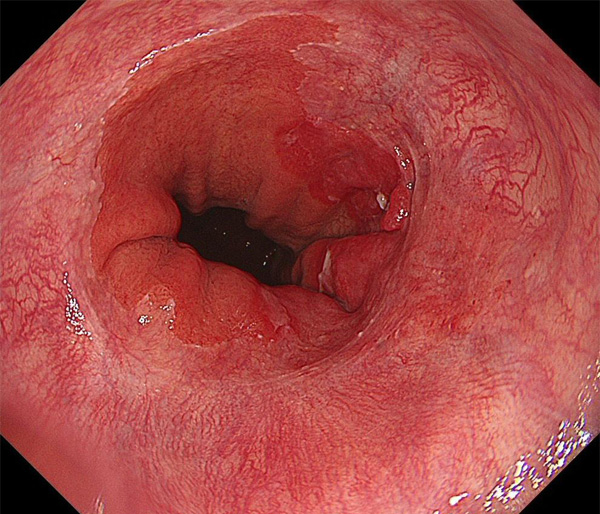

内視鏡所見と病理組織像の1対1対応が可能な症例を公募いたします。主にLSBEに発生した早期癌(HGDを含む)を対象としますが、興味深い症例であればSSBE癌でも結構です。採否は世話人へご一任ください。

症例呈示希望者は応募用紙に記入の上、代表的な内視鏡(2枚)、切除標本(新鮮、固定)、切り出し図、マッピング、代表的組織像とともに、Barrett 食道研究会事務局 barrett.shinshu@gmail.comへお申し込み下さい(10MB以下でお願い致します)。

特に、本邦では極めて稀なlong segment Barrett’s esophagus(LSBE)から発生した早期癌は、診断に難渋する場合も多く、欧米ではランダム生検による検出が標準的とされています。背景のBarrett食道もろとも全体を内視鏡切除+ラジオ波焼灼する欧米と異なり、ESDで内視鏡的な局所切除が基本の本邦では、存在診断+範囲診断(特に水平)を的確に行うことが不可欠です。

そのためには、一流の病理医による組織学的診断とエキスパート内視鏡医による拡大内視鏡像との一対一対応を徹底的に行うことで、『本来、見えないであろう拡大所見の先にある組織構築像が診えてくる』所まで内視鏡診断レベルを上げていく必要があります。その実現には、一対一対応を追究した症例(特にLSBE発生例)1例でも多く経験するしかありません。本研究会でBarrett食道腺癌(LSBE発生早期病変)を共に学び、拡大内視鏡像の一歩先を診るスキルを習得しましょう!一人でも多くの皆様のご参加をお待ちしています。

海外で講演やライブを行う度に、日本と欧米ではBarrett食道癌診断法に大きな乖離がある事を実感します。なぜ、彼らは内視鏡で診断せず、ランダム生検に頼るのか?

私は、Barrett食道癌はHGDも含め、内視鏡による存在診断、範囲診断が可能と信じて来ました。しかし最近、NBI拡大観察を併用しても側方範囲診断が不可能なLSBE症例を経験しました。診断技術を向上させるためには、多くの症例を診るしかありません。そこで、Barrett食道に造詣の深い先生方に世話人をお願いし、Barrett食道研究会を立ち上げることに致しました。全国からLSBE症例を集め、内視鏡的、組織学的診断に迫りたいと思います。皆様のご参加をお待ち致します。